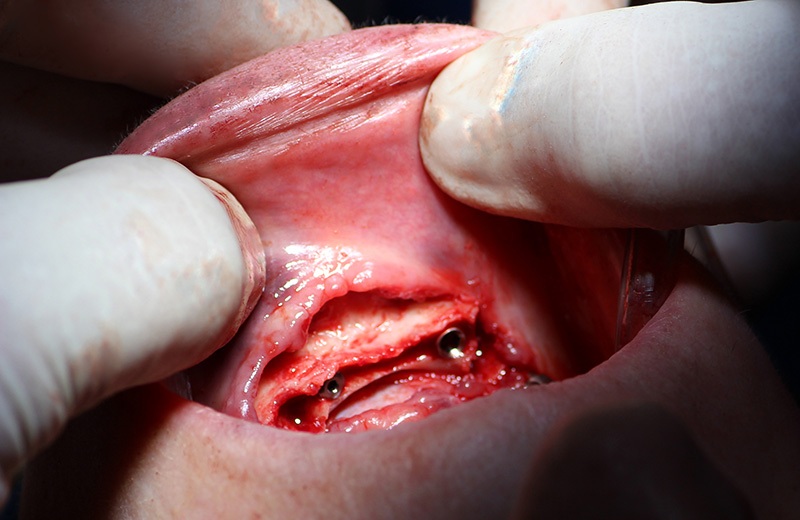

25-ого октября в учебном центре Стом-Лайн был проведен мастер-класс на тему «Одномоментная имплантация с аугментацией (наращиванием) кости, с использованием имплантатов Alfa Gate Dental Implants». Мастер-класс провел главный врач-стоматолог клиники «Нюанс» в Москве Мхитар Казарян.

Мастер-класс начался с обсуждения предстоящей операции и исследования компьютерной томографии, после чего участники смогли присутствовать на операции или следить за ней из учебного центра.